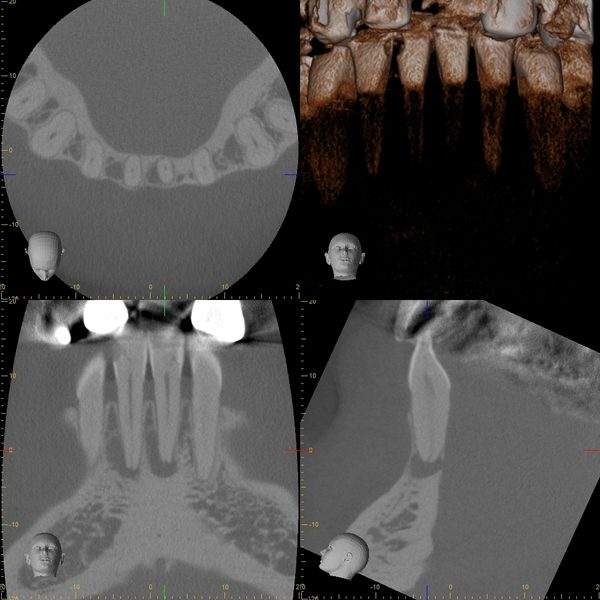

術前のレントゲン写真とCT画像と、お口の中の写真です。下の前歯2本(#31,41)です。

2本の根の周りに黒い影(透過像)があるのが分かります。

術後6ヵ月後のレントゲン写真とCT画像です。

術前にあった根の周りの黒い影は縮小して改善しているのが分かります。